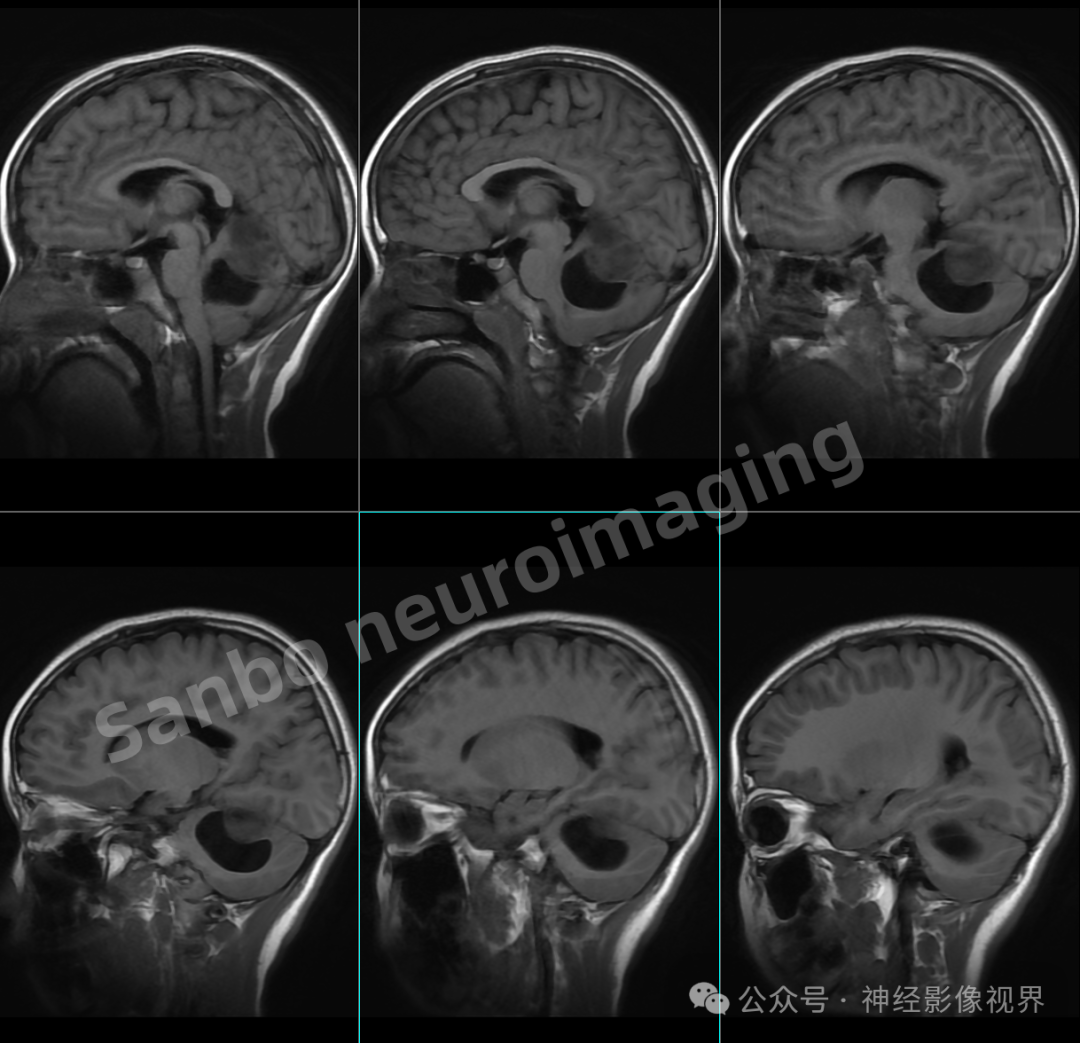

3、T2W1高信号的含义T2W1高信号是核磁共振检查中的一种表现在MRI检查中,不同的组织或病变会在特定的序列下呈现出高或低的信号T2W1序列是MRI中的一种常用序列,用于评估组织的T2弛豫时间星形细胞瘤与T2W1高信号星形细胞瘤是脑瘤的一种,当星形细胞瘤在T2W1序列上呈现高信号时,这通常是一个提示;星形细胞瘤是否属于癌症不能一概而论,需结合其病理分级判断星形细胞瘤的病理分级从I级到IV级,不同级别的肿瘤恶性程度差异显著III级星形细胞瘤通常被视为良性或低度恶性肿瘤这类肿瘤生长缓慢,细胞形态接近正常,侵袭性较弱例如,弥漫性星形细胞瘤多发生于大脑白质,虽可能局部浸润,但极少;间变性星形细胞瘤是一种出现在脑部或脊髓中的恶性肿瘤以下是关于间变性星形细胞瘤的详细解释发病部位与人群主要出现在脑部或脊髓中成人和儿童均可发病,但临床表现有所不同临床表现成人通常先出现癫痫症状,随后可能逐渐出现瘫痪失语精神改变,最终可能导致颅内压增高儿童由于年龄较小;星形细胞瘤是胶质瘤的一种具体类型,属于胶质瘤中占比最高的亚类约占65%胶质瘤是源于神经胶质细胞的肿瘤总称,涵盖星形细胞瘤少突胶质细胞瘤室管膜瘤等多种病理类型因此,星形细胞瘤与胶质瘤的关系可类比为“苹果与水果”的从属关系发病部位与症状差异星形细胞瘤多发生于大脑的额颞叶区。